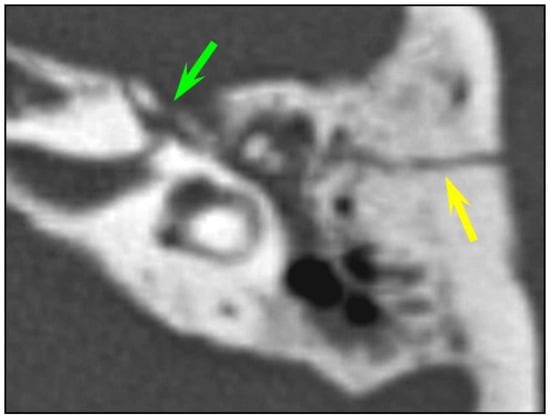

In total, fractures involved the bony labyrinth in 11 cases and extended into the following structures: semi-circular canals (posterior semi-circular canal, n = 3; superior semi-circular canal, n = 2), vestibule (n = 3), cochlea (n = 1) and the vestibular aqueduct (n = 2). Involvement of the internal auditory canal was seen in two cases. Fracture lines extended into the petrous apex in 10/126 (7.9%) of all temporal bone fractures, and fractures along the osseous structures surrounding the facial nerve were seen in 8/126 (6.3%) cases. The fractures lines involved the geniculate fossa in four cases (Figure 2), the facial nerve canal in the tympanic cavity in two cases and the bony structure surrounding the second genu of the facial nerve in two cases, respectively. Air in the tympanic facial canal without a visible fracture line was present in one case.

Figure 2. Facial canal injuries. Fracture of the left temporal bone in a 25-year-old man with peripheral facial palsy after a fall. CT of the left temporal bone: longitudinal fracture (yellow arrow) with associated bony fragments in the geniculate ganglion fossa (green arrow) consistent with a geniculate facial canal injury.